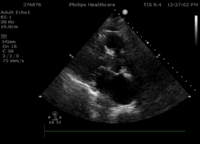

此患者为86岁男性,因“突发胸痛、胸闷28小时”入院,诊断为急性心肌梗死,合并快室率房颤、肺部感染、慢性肾功能衰竭,入院后在积极药物及IABP辅助下心衰仍难以控制,查体出现心尖部收缩期杂音,心脏彩超提示“二尖瓣前瓣脱垂(A2区为主)并重度关闭不全,瓣尖见条索状回声随心动周期摆动”(视频1、视频2 、视频3)。术前,武汉亚总和亚心医院结构性心脏病多学科团队对该患者病情进行了反复讨论,认为该高龄患者急性心肌梗死后出现机械并发症,且合并多器官功能不全,心功能不全难以纠正,死亡率极高,外科开胸手术风险极高(STS评分>30),决定选择微创经导管二尖瓣夹合术。

3月30日患者先在全麻下进行TEE(经食道超声心动图)再次评估瓣膜情况(视频4、视频5、视频6 ),确定为二尖瓣前组乳头肌断裂致二尖瓣前瓣脱垂并重度返流,其脱垂部位、瓣叶结构、瓣口面积等适合进行二尖瓣夹合术。术中IABP辅助,ECMO湿备,穿刺右侧股静脉,在TEE指导下顺利穿刺房间隔,随后送入二尖瓣夹合系统,在超声指导下于二尖瓣A2/P2区植入一枚Mitraclip XTR夹合器(视频7),术后TEE评估返流程度从5+降至1+(视频8 ),夹合结果满意,二尖瓣呈双孔启闭(视频9 ),术后二尖瓣平均跨瓣压差1mmHg(图1),收缩期肺静脉返流消失(图2 ),手术总耗时80min。香港亚洲医疗中心林逸贤教授通过视频连线进行手术全程技术支持。